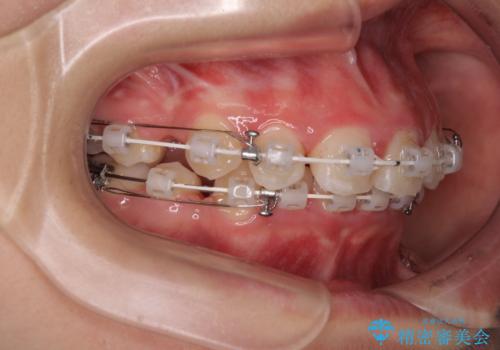

- 矯正装置

- 審美装置

- 下唇の上に乗っかってしまうくらい前歯が飛び出していることを気にして来院された患者様です。

唇を閉じようとするとオトガイ部に力が入ってしまい、うまく閉じることができない状態であったため、上下左右の第一小臼歯4本を抜歯して、ワイヤー装置にて矯正治療を行うこととしました。